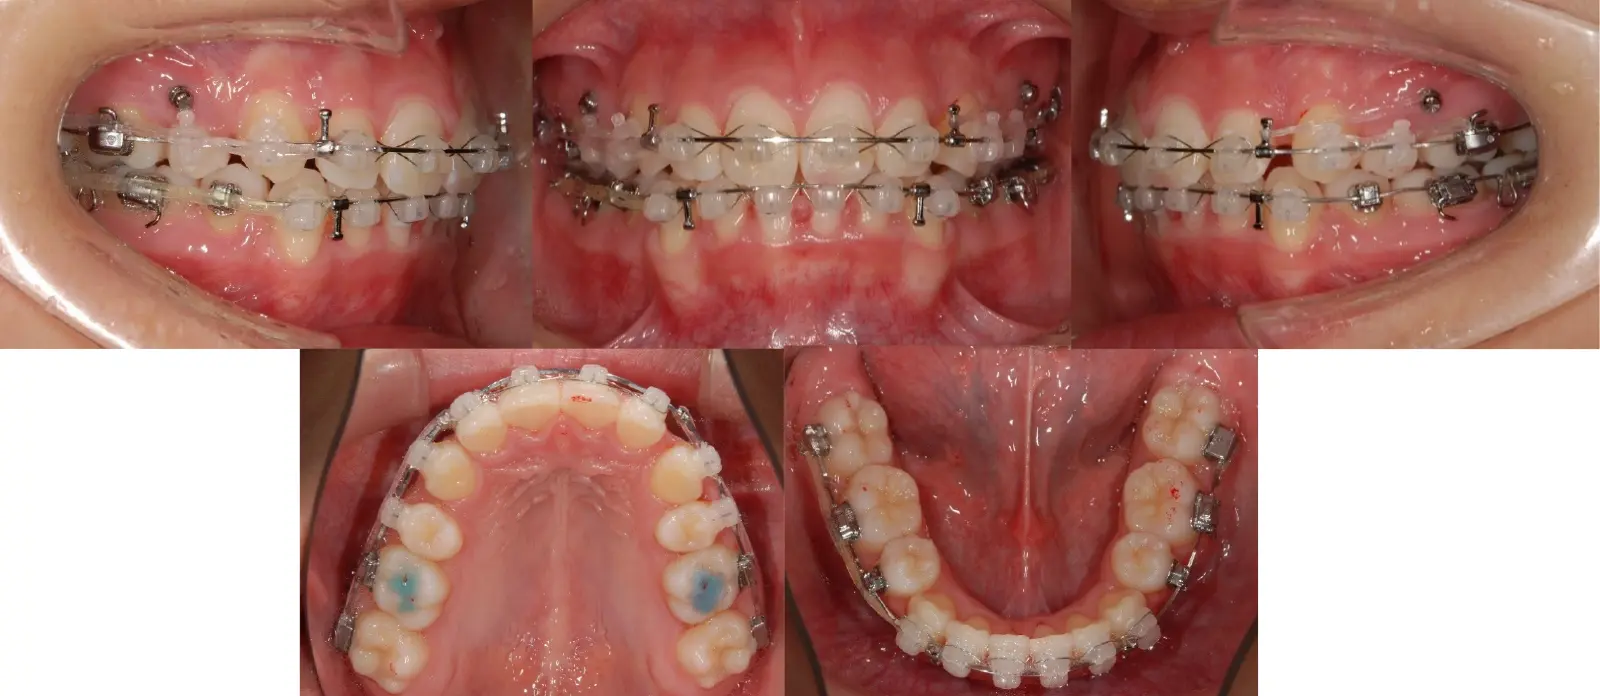

アングルⅡ級叢生を伴う上顎前突症

- 主訴

出っ歯

- 年齢

20代

- 治療期間

2年6ヶ月

- 治療回数

29回

- 治療に用いた主な装置

カスタムメイド型リンガルブラケット矯正装置 (WIN)

- 治療費

1,400,000円(税別)トータル料金

- 抜歯部位

上顎の中切歯が失活歯で、根尖病変が存在したため、上顎中切歯と下顎左右側第一小臼歯を抜歯。